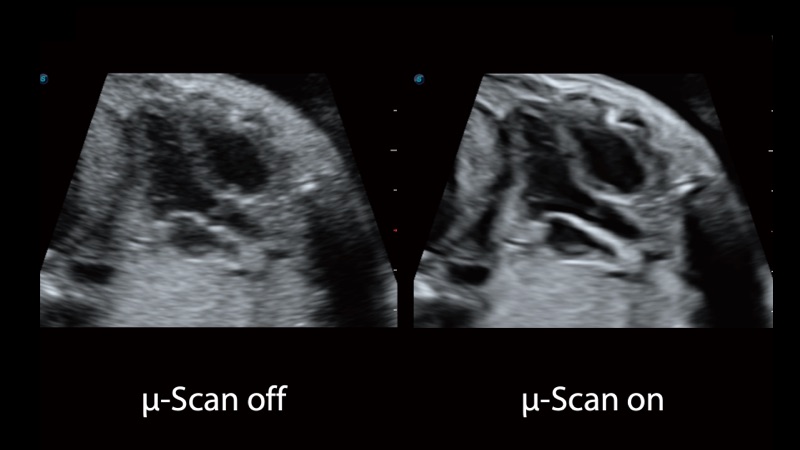

開立醫(yī)療通過不斷的技術(shù)創(chuàng)新,為大眾的生命健康提供持續(xù)關(guān)愛。P12 Plus采用全新一代超聲成像平臺,新平臺旨在將真實還原組織解剖結(jié)構(gòu)作為首要目標(biāo)。平臺采用全新集成化硬件模塊,搭載新一代芯片,系統(tǒng)性能得到大幅提升,為您的診斷提供了豐富的臨床信息。優(yōu)異的圖像表現(xiàn),豐富的探頭配置,全面的應(yīng)用功能,為您日常診斷提供了可靠的助手。

P12 Plus

彩色多普勒超聲診斷系統(tǒng)